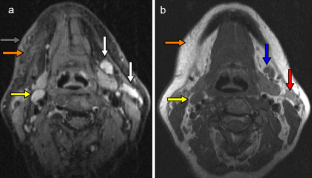

The aim of the study was to determine objective radiological signs of danger to life in survivors of manual strangulation and to establish a radiological scoring system for the differentiation between life-threatening and non-life-threatening strangulation by dividing the cross section of the neck into three zones (superficial, middle and deep zone). Forensic pathologists classified 56 survivors of strangulation into life-threatening and non-life-threatening cases by history and clinical examination alone, and two blinded radiologists evaluated the MRIs of the neck. In 15 cases, strangulation was life-threatening (27%), compared with 41 cases in which strangulation was non-life-threatening (73%). The best radiological signs on MRI to differentiate between the two groups were intramuscular haemorrhage/oedema, swelling of platysma and intracutaneous bleeding (all p = 0.02) followed by subcutaneous bleeding (p = 0.034) and haemorrhagic lymph nodes (p = 0.04), all indicating life-threatening strangulation. The radiological scoring system showed a sensitivity and specificity of ≈70% for life-threatening strangulation, when at least two neck zones were affected. MRI is not only helpful in assessing the severity of strangulation, but is also an excellent documentation tool that is even admissible in court.